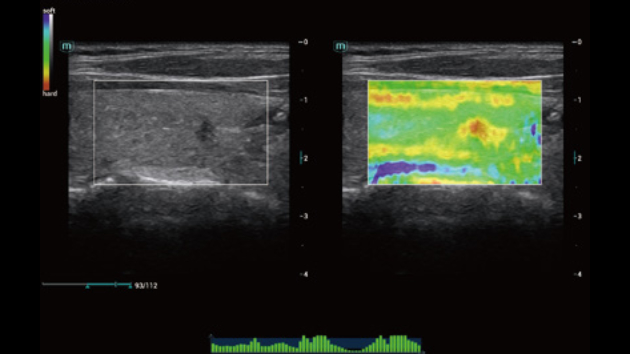

Comprehensive Imaging Solutions Powered by ZST+

The ZST+ platform is an extraordinary innovation, representing an ultrasound evolution. Transforming ultrasound metrics from conventional beam-forming to channel data based processing. It overcomes the traditional trade-off limitation among spatial resolution, temporal resolution and tissue uniformity, delivering exceptional image quality for infinite imaging solutions with non-stop improvements.